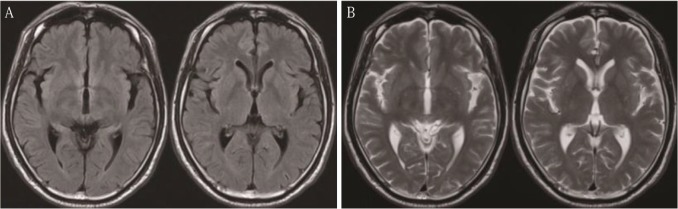

62歲男性,主訴復(fù)視病史1個月。60歲時,患者有緊張性頭痛,曾行磁共振成像(MRI)檢查,未見異常表現(xiàn)(圖1)。MRI兩年后,患者行計算機斷層掃描(CT)和磁共振成像(MRI)檢查復(fù)視。CT顯示腫瘤呈增強形態(tài),直徑3cm,松果體區(qū)可見鈣化(圖2A)。腫瘤在t1加權(quán)MRI上呈等強度(T1WI,圖2B);T2WI微低信號(圖2C)和流體衰減反演恢復(fù)圖像(圖2D);T2* WI低信號明顯(圖2E),擴散WI明顯(圖2F), T1WI上釓異質(zhì)增強(圖2G)。釓增強T1WI矢狀面顯示垂體神經(jīng)區(qū)未見腫瘤(圖2H)。腦積水是由于腫瘤引起導(dǎo)水管狹窄所致。病人轉(zhuǎn)到我們醫(yī)院治療。入院后復(fù)視好轉(zhuǎn),眼球運動充分平穩(wěn)。經(jīng)簡易心理狀態(tài)檢查和韋氏成人智力量表檢查,其心理功能輕度惡化。他的下面血清腫瘤標(biāo)記物在正常范圍:甲胎蛋白,β人體絨毛膜促性腺激素(βhcg)、癌胚抗原、β2-microglobulin,促黃體激素5.2個人/毫升(參考價值:1.7 - -11.2)、促卵泡激素9.2個人/毫升(參考價值:2.1 - -18.6),和睪酮482.0毫微克/分升(參考價值:220.9 - -715.8)。腦血管攝影顯示一個微弱的腫瘤染色沒有任何動靜脈分流。CT檢查未發(fā)現(xiàn)有轉(zhuǎn)移到腦的腫瘤。因此,在鑒別診斷時要考慮多種腫瘤,如松果體實質(zhì)腫瘤、神經(jīng)膠質(zhì)瘤、不明來源的轉(zhuǎn)移性腫瘤和海綿狀血管瘤。隨后患者行內(nèi)鏡下活檢和三腦室造口術(shù),經(jīng)右額冠狀前刺孔及可操作的電視鏡檢查。腫瘤很容易在松果體區(qū)發(fā)現(xiàn)一個灰色腫塊,包含舊時出血和鈣化(圖3A),懷疑轉(zhuǎn)移到漏斗部(圖3B)?;顧z標(biāo)本取自幾個不同的部位?;顧z時腫瘤有少量出血,沖洗可輕易止血。術(shù)后無并發(fā)癥發(fā)生。術(shù)中腦脊液(CSF)β-HCG為0.12 mIU/mL,略升高。腦脊液中未檢測到腫瘤細(xì)胞。組織病理學(xué)上,腫瘤呈2細(xì)胞型,上皮樣細(xì)胞大,淋巴細(xì)胞小。前一個細(xì)胞經(jīng)胎盤堿性磷酸酶(圖4C)和c-kit(圖4D)染色呈陽性。未觀察到其他GCT成分。因此,此腫瘤的組織病理學(xué)診斷證實為純生殖細(xì)胞瘤?;颊呓邮軉蝿┝糠派渲委?腦室播散小劑量預(yù)防照射(25.2 Gy),原發(fā)腫瘤部位放射增強(25.2 Gy), MRI未見脊髓播散征象。放療后腫瘤完全消失,無神經(jīng)功能缺損。腦脊液β-HCG水平恢復(fù)正常。經(jīng)過4年的放射治療后,連續(xù)的MRI隨訪研究和β-HCG檢測沒有發(fā)現(xiàn)腫瘤復(fù)發(fā)。

圖1:入院前2年進行磁共振成像。注意,在液體衰減反轉(zhuǎn)恢復(fù)圖像(A)或t2加權(quán)圖像(B)上,松果體區(qū)未見腫瘤。